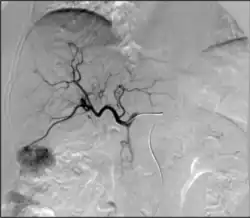

Angiography: Imaging the blood vessels to look for abnormalities with the use of various contrast media, including iodinated contrast, gadolinium based agents, and CO2 gas.[3]

Angiography: Sometimes referred to as traditional angiography, catheter angiography or digital subtraction angiography (DSA). A small needle is inserted into a blood vessel, then exchanged for a catheter over a wire. The catheter is directed at the vessel to be studied, and contrast is directly injected to evaluate the lumen under video X-ray. This is an older technique than modern CT angiography or MR angiography, but provides unique advantages. With a catheter in place, provocative maneuvers can be performed such as breath holds or instillation of vasodilators, to evaluate a patient's blood flow dynamically. This can reproduce symptoms and identify functional abnormalities in a vessel that a static CT or MR imaging cannot.[80][81] Angiography provides the basis for all endovascular therapy.